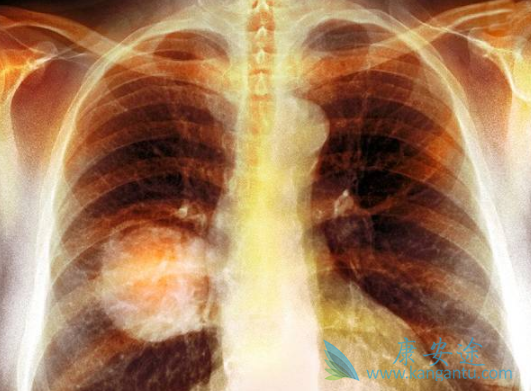

纳武利尤单抗(纳武单抗)用药信息:用法用量:3mg/kg,两周一次或2 mg/kg,三周一次。适应症:表皮生长因子受体(EGFR)基因突变阴性和间变性淋巴瘤激酶(ALK)阴性、之前接受过含铂方案化疗后疾病进展或不可耐受的局部晚期或转移性非小细胞肺癌(NSCLC)成人患者。